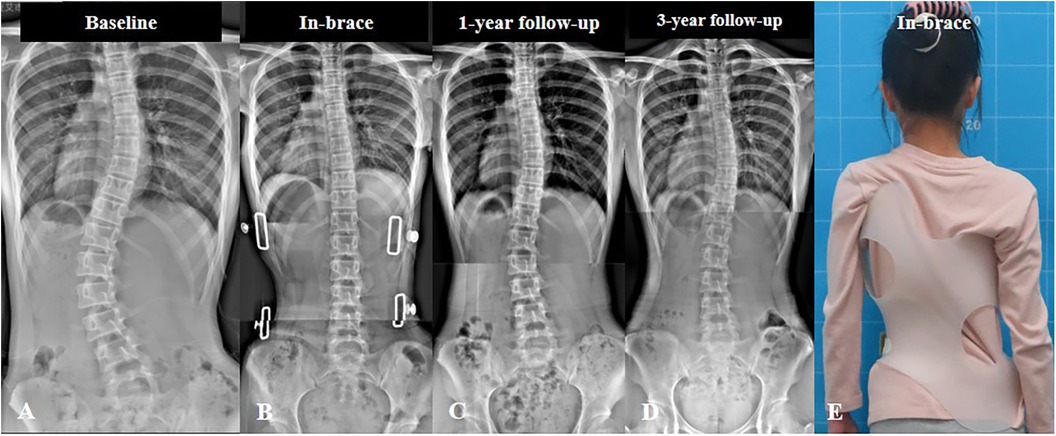

تختلف خطة العلاج حسب شدة الاعوجاج ومرحلة النمو، وتشمل:

المتابعة الدورية في الحالات البسيطة

العلاج الطبيعي وتمارين مخصصة

استخدام حزام اعوجاج العمود الفقري في بعض الحالات

التدخل الجراحي في الحالات الشديدة فقط

أغلب الأطفال لا يحتاجون إلى جراحة عند الالتزام بالعلاج في الوقت المناسب.

هل يمكن الوقاية من تفاقم الاعوجاج القطني؟